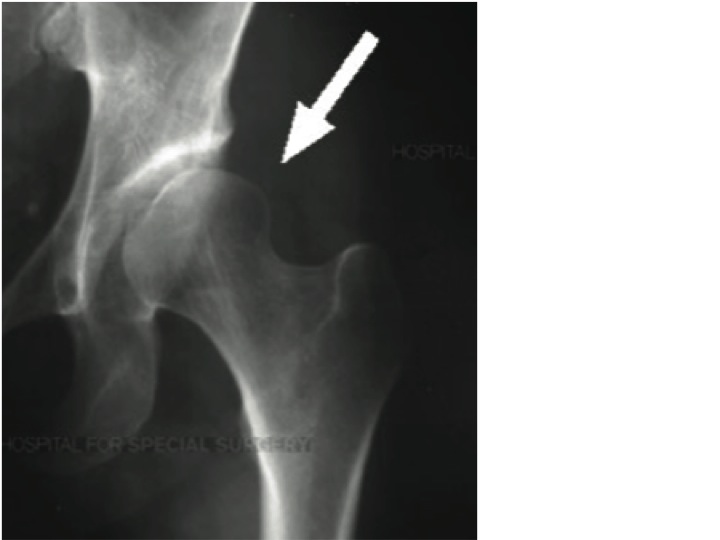

Femoral Acetabular Impingement Savannah Orthopedics Runners Hip Impingement Hip joint impingement, referred to as femoroacetabular impingement, leads to sharp pain after running and during running, which may also radiate to the groin. Strength training and physical therapy are critical for the transition back into running. The hip joint is relearning how to absorb the running forces. This can significantly impact their. That triggers pain in the groin area. Runners Hip Impingement.